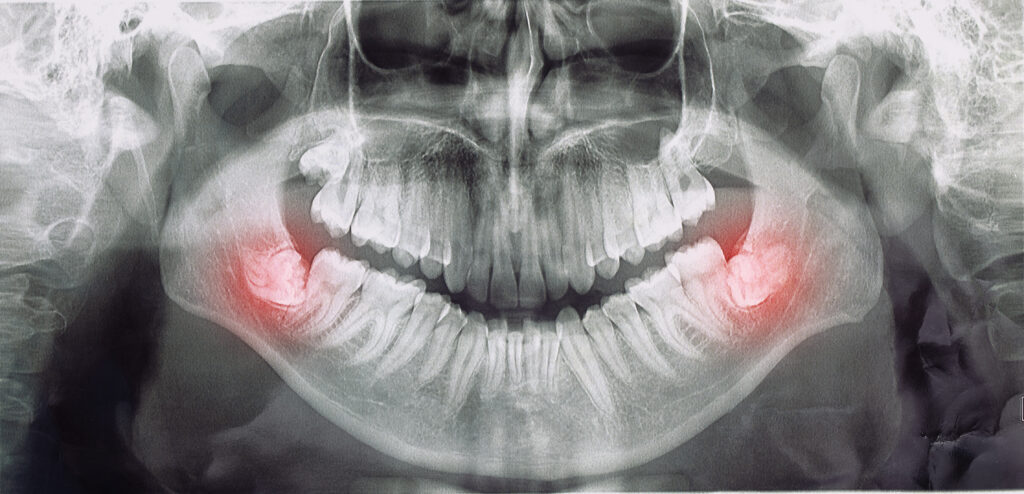

What is impacted Teeth? and Symptoms of impacted teeth

Impacted teeth are teeth that we expect to erupt into our mouth but do not erupt for a variety of reasons and instead remain in our jaws under the gum or bone.

The most common impacted teeth are the wisdom teeth. Canine teeth, premolars, and extra teeth known as’surnumerers’ may also be found in our jaws.

Impacted teeth refers to teeth that do not erupt into the mouth properly. They remain fully or partially embedded in the jawbone or gums. The most commonly impacted teeth are wisdom teeth, or the third molars. But canines and premolars can also become impacted.